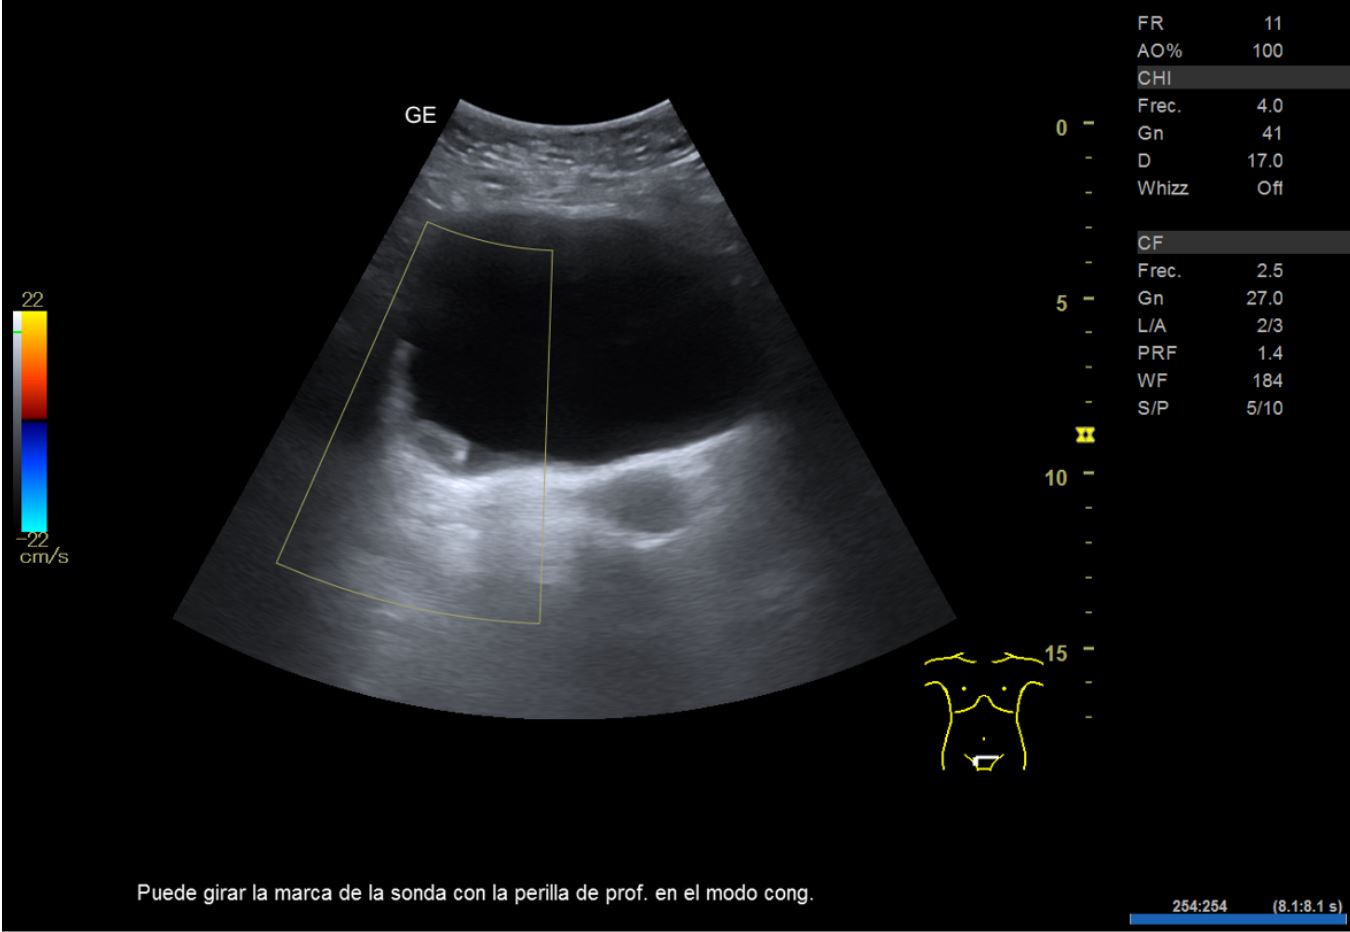

• Ecografía clínica renovesical: riñones con diámetro dentro de la normalidad. Relación cortico-medular normal. Pedículo renal Doppler normal. No se observan litiasis. Vejiga repleta, paredes finas, se observa imagen hipoecogénica en pared posterior lateral derecha que no capta señal Doppler, de unos 2,21 cm de diámetro aproximadamente. Volumen premiccional 290,86 ml, volumen posmiccional 25,54 ml.

En primer lugar se derivó a ginecología por sospecha de sangrado de origen ginecológico donde visualizan ecográficamente un grosor endometrial de 5-6 mm y realizan una biopsia endometrial con resultado de escasos fragmentos superficiales de endometrio atrófico. Tras descartar origen ginecológico y ante la persistencia del sangrado, se orienta como hematuria monosintomática y se realiza una ecografía en el centro de Atención Primaria donde se visualiza imagen hipoecogénica dependiente de la pared vesical.